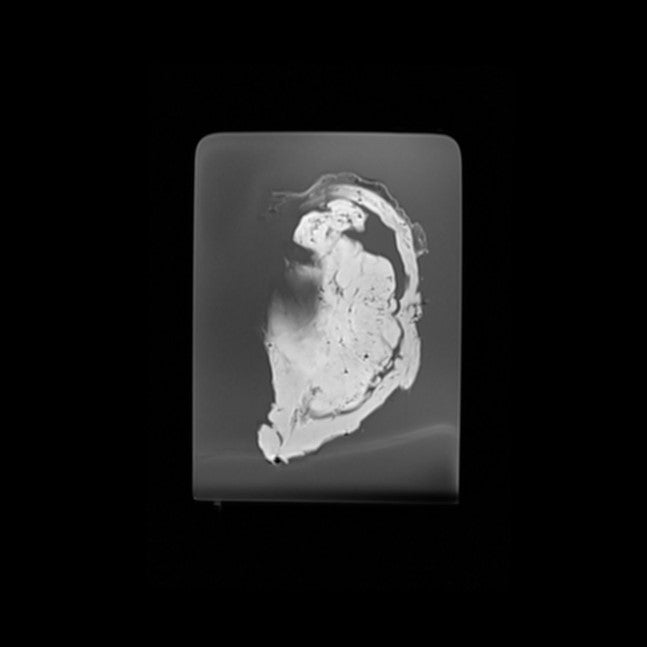

Bladder, Prostate, Kidney, Ureter - Benign Prostate Hyperplasia